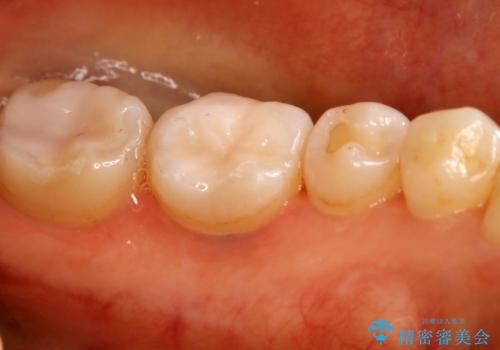

- 左下奥歯のメタルインレーを白くしたいと希望された患者様です。

形態、切削量などを考慮し、セラミックインレーにて治療を行いました。

メタルインレー、う蝕除去後にCRにて裏層した上で、形成・印象を行いました。